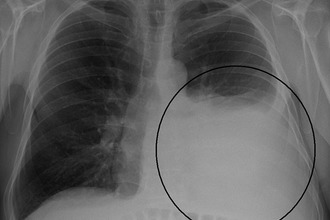

Травматические повреждения ребер и грудной клетки часто вызывают болевые ощущения, усиливающиеся при глубоком дыхании или кашле. Рентгенологическое исследование после травмы помогает уточнить характер повреждений и определить подход к лечению. Важно своевременно установить диагноз, так как переломы ребер могут привести к пневмотораксу — серьезному состоянию, при котором воздух накапливается в плевральной полости. Это может вызвать спадение легочной ткани и нарушить функции дыхания и кровообращения.

Пневмоторакс может возникнуть не только в результате травмы. В редких случаях он развивается у пациентов с абсолютно здоровыми легкими из-за физической нагрузки или сильного кашля.

При спонтанном пневмотораксе пациенты испытывают резкую боль в грудной клетке с пораженной стороны, которая усиливается при дыхании, кашле или движении. Лечение таких случаев проводится в хирургическом отделении.